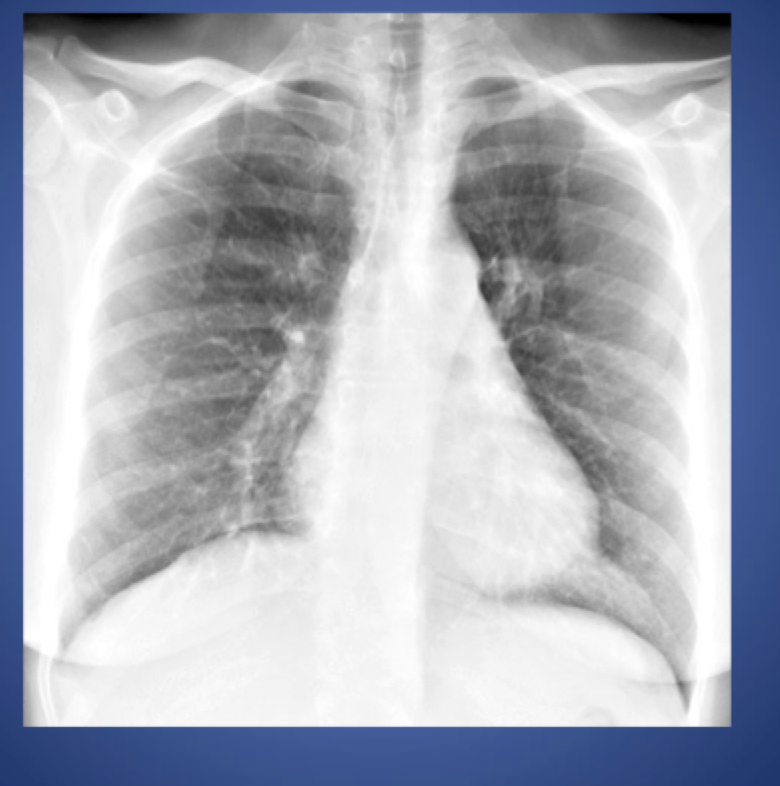

Chest xray pink puffer

A

-Hyperinflation, FLAT diaphragms

-Vascular markings DECREASE

-Parenchymal BULLAE*

Sx:

-DYSPNEA severe

- Using accessory muscles for inspiration

-Chest is QUIET -> no congestion in lungs

-NO peripheral edema